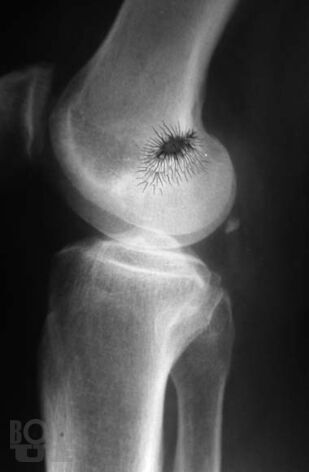

Практическое руководство «Рентгенодиагностика позвоночника для мануальных терапевтов» обобщает многолетний опыт сотрудничества автора – рентгенолога с мануальными терапевтами и освещает проблемы лучевой диагностики с точки зрения мануальной терапии. В руководстве представлен метод системного анализа рентгенограмм позвоночника. Особое внимание уделено клиническим аспектам применения данного метода в практике мануальной терапии: отражены методики экспресс-диагностики пространственного положения структур краниовертебральной зоны, позвоночника и крестца, описаны способы распознания, регистрации, хранения и передачи данных об индивидуальных характеристиках позвоночника каждого больного. Приведены классификации, рентгенологические проявления и особенности диагностики аномалий развития позвоночника в практике мануальной терапии. Показаны возможности и перспективы метода системного анализа рентгенограмм позвоночника для совершенствования лучевой диагностики в мануальной терапии и в восстановительной медицине. Руководство содержит большое количество рентгенограмм, схем, рисунков и таблиц.